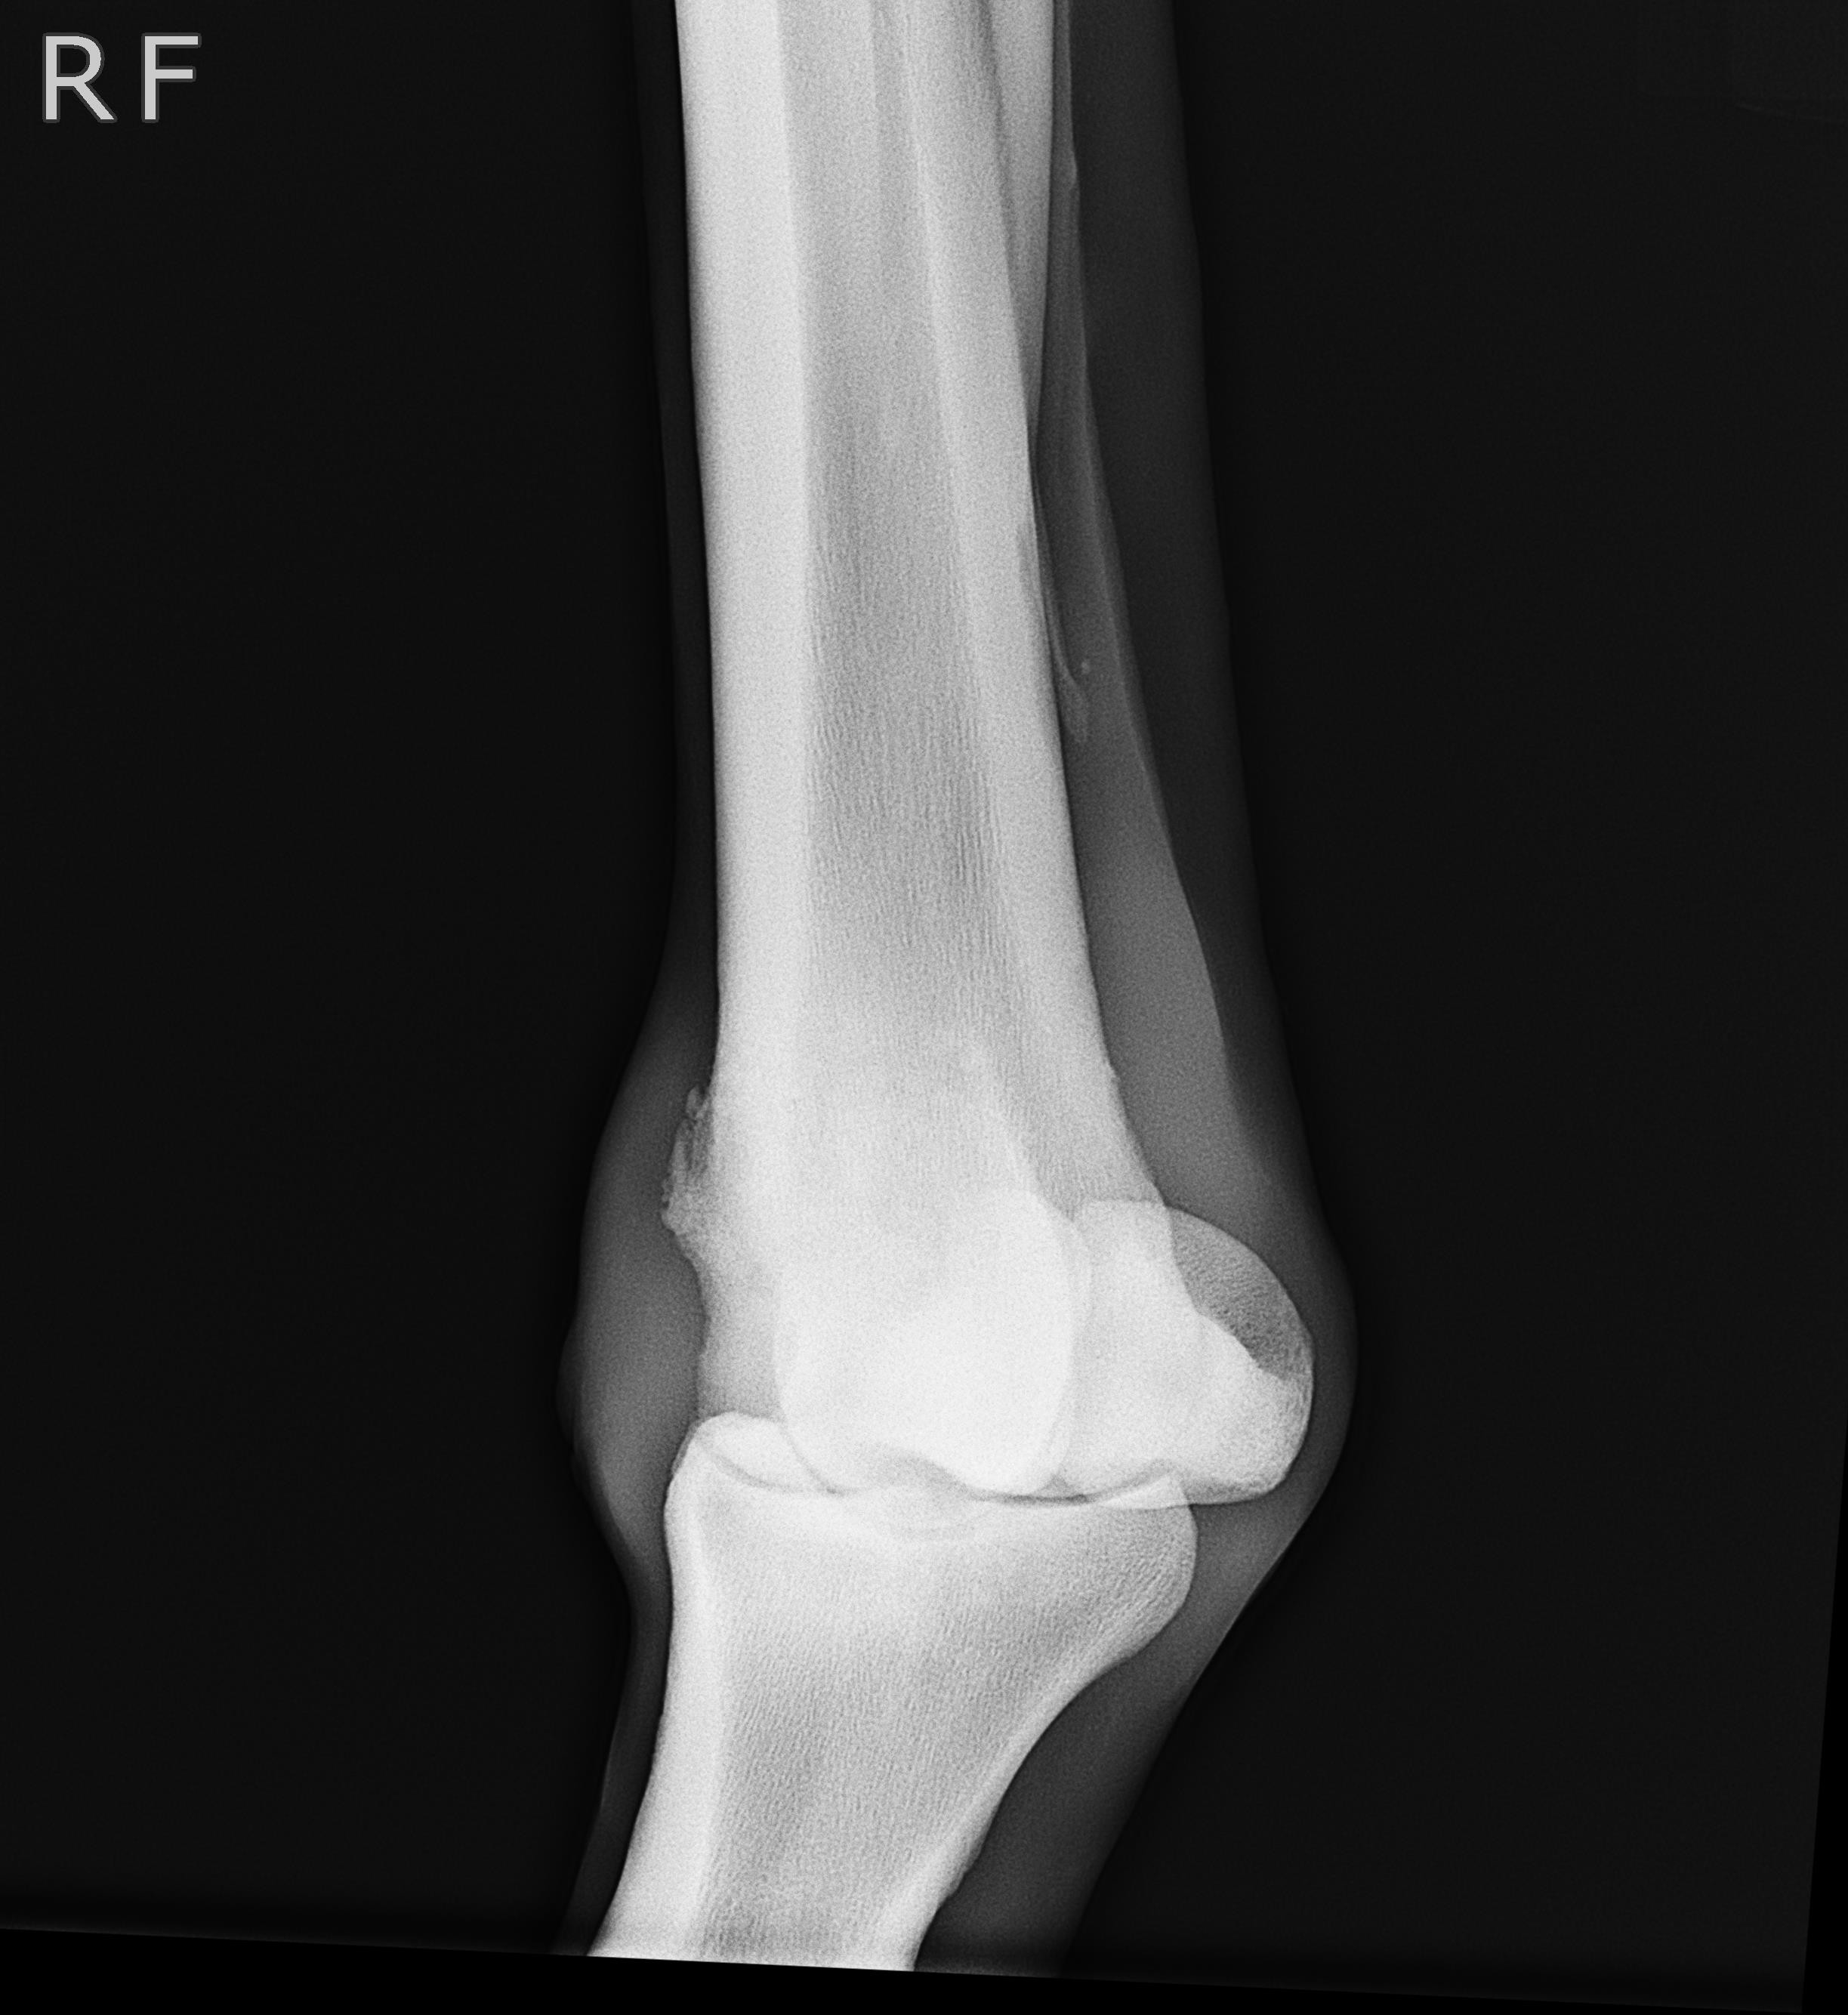

アユ号は笠松競馬、1月8日勝利後右前脚球節全面に骨膜炎が出ました。

X-Pも参考にしてください。